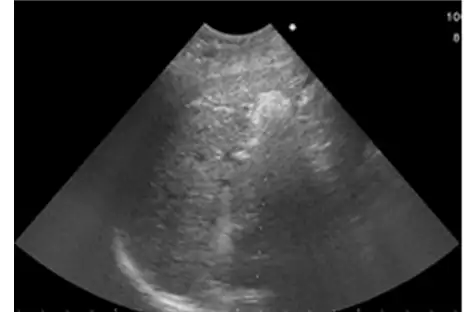

• 造影超音波にて治療効果を確認

造影超音波にて治療効果を確認